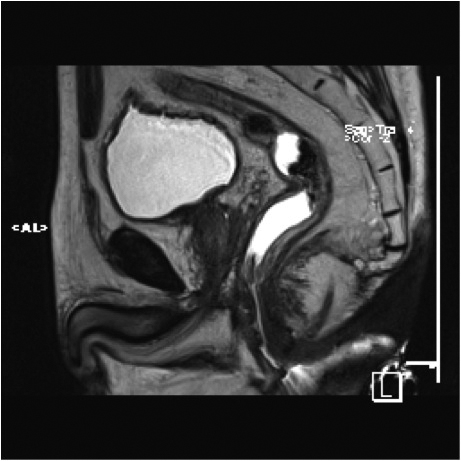

Fig1. Pacient cu neoplasm rectal stadiul IIIC (T3; N2; M0) confirmat bioptic, adenocarcinom mixt G2

a-d imagini T2 ponderate în plan sagital, oblic axial și oblic coronal – masă tisulară dezvoltată superior de joncțiunea anorectală, lateral dreapta, cu minimă extensie la nivelul grăsimii mezorectale și limfoganglioni mezorectali cu diametru de până la 10 mm;